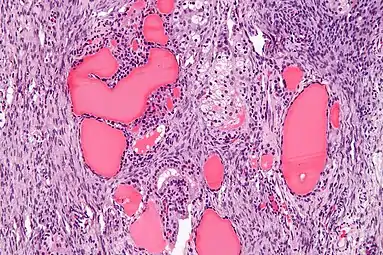

| Micrograph of a struma ovarii. Characteristic thyroid follicles are seen on the right, and ovarian stroma on the left. H&E stain. | |

Low magnification Struma ovarii

High magnification Struma ovarii